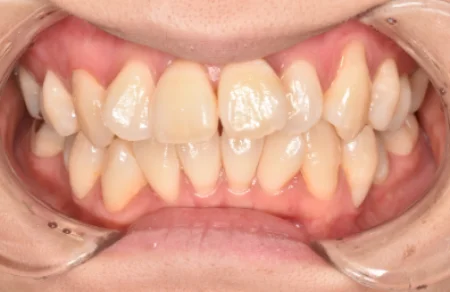

セラミック 2023.0130代女性「上の歯並びを綺麗にしたい」セラミックの被せ物により、ガタガタに生えていた前歯の見た目を短期間で改善した症例